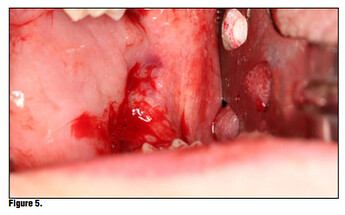

Once the product is removed from the packaging, simply place it onto the wound or extraction site dry and with a matter of 15-20 seconds the material absorbs the wound fluids and turns into a gel and fills the void (Figure 5). Once the site is properly sealed with the material it can be properly rinsed and should not become dislodged. In this case, a suture was placed in conjunction with the product, but in many cases this may not be necessary. A practitioner’s judgment should be utilized in determining if a suture is required in conjunction with the product (Figure 6). The site itself can be sutured, but is not necessary. Nevertheless, the site should not be sutured in place using primary closure as the product needs to be in contact with oral environment and have proper drainage. It is not recommend to suture with primary closure as the creation of a closed contaminated space could be created and this may increase the risk for abscess formation.